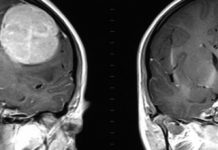

Mitochondrial 'smart bomb' could treat brain tumors

Researchers from Houston Methodist Hospital allow us a so-called mitochondrial smart bomb that can be used to deal with brain tumors by attacking the cell's power source, according to...